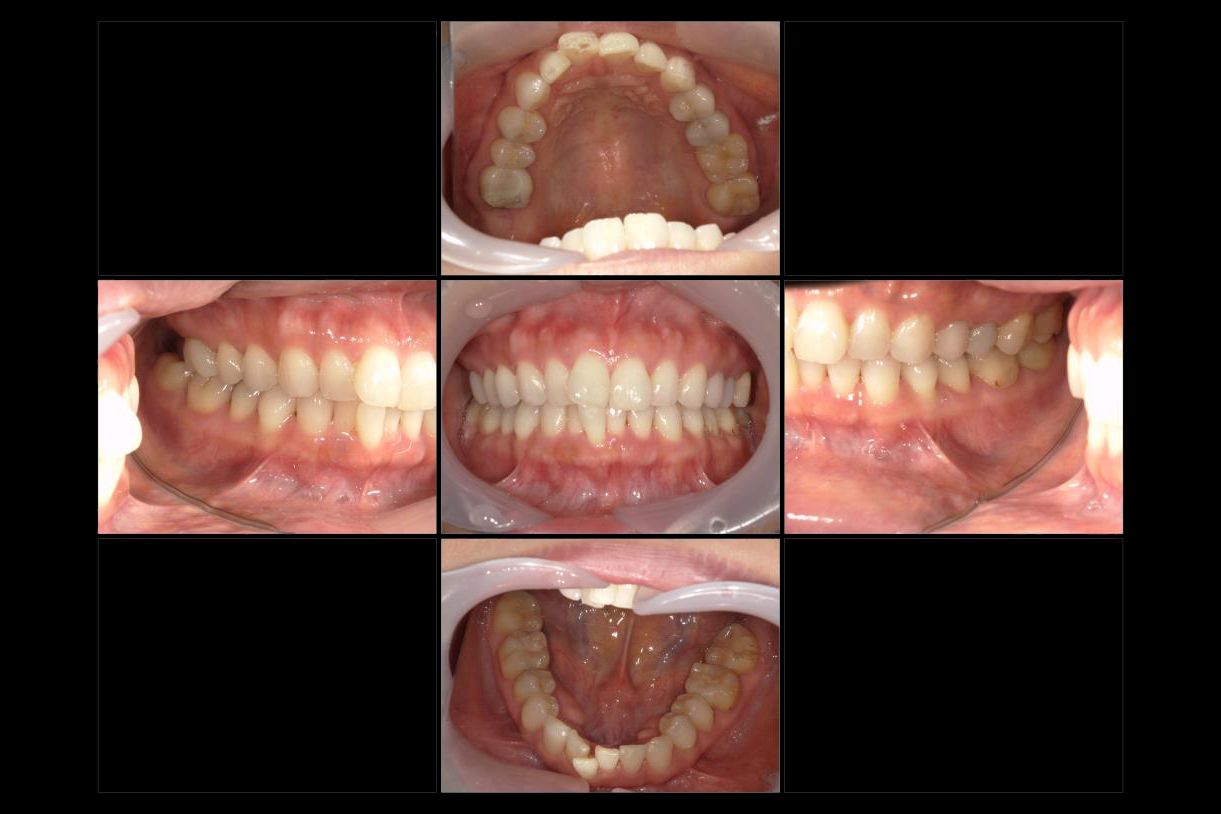

初診時年齢:40代男性

治療:全体矯正

治療法:マウスピース型矯正装置(インビザライン)

治療期間:3年

費用:902,000円(税込)

リスク・副作用:装置装着による違和感、歯の移動時の痛み